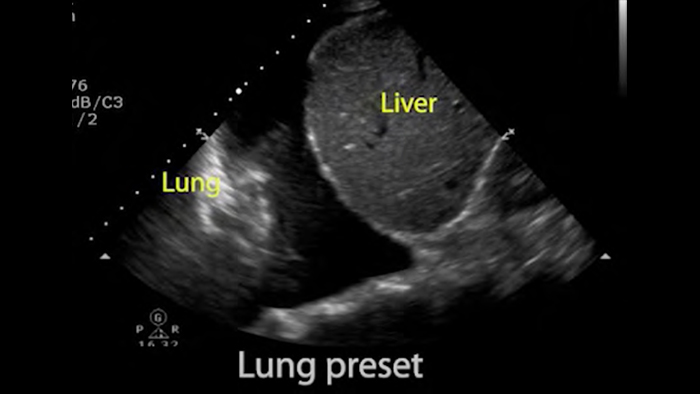

Use Lumify for airway and pulmonary assessment

Lumify POCUS solutions can help you detect the endotracheal tube within the trachea, assist in emergent cricothyrotomy procedures, diagnose pleural effusion and interstitial alveolar diseases.